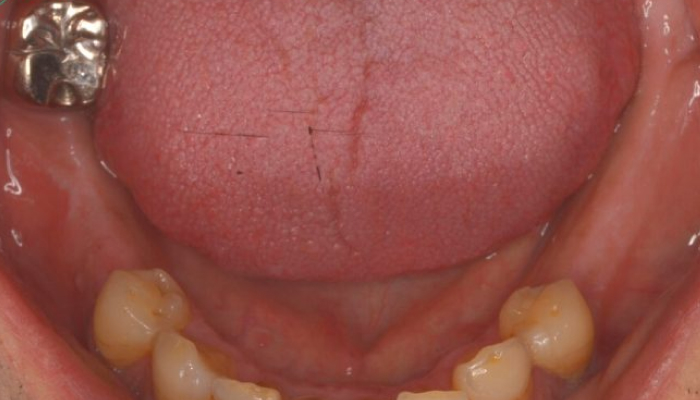

歯を1本失う虫歯や歯周病が原因で、1本の歯を失うことから始まります。特に「第一大臼歯」と呼ばれる一番奥の歯が最初に抜けるケースが多く、それに続いて「第二大臼歯」を失うことが一般的です。この段階では、部分入れ歯やブリッジなどの治療法が選択されることが多いですが、これらの方法は隣接する健康な歯に負担をかける可能性があります。

歯を複数本失う部分入れ歯やブリッジ治療により、周囲の健康な歯に負荷がかかり始めます。その結果、支えとなる歯が次第に弱くなり、複数の歯を失うリスクが高まります。この段階では、噛む力のバランスが崩れ、さらにお口の健康状態が悪化する傾向にあります。